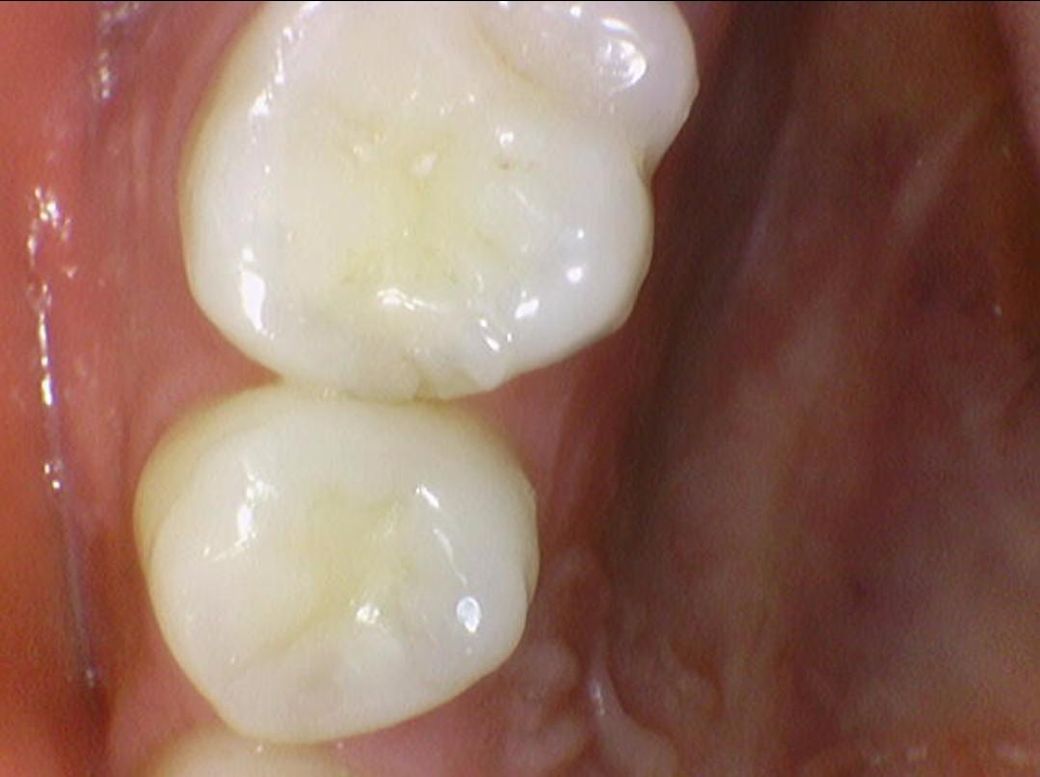

밑에 구강내부 사진(16,17,26,27번 치아)들에서

치료가 반드시 필요한 치아는 몇번째 사진 이런식으로 설명 부탁드립니다

• 1번 째 사진

• 2번 째 사진